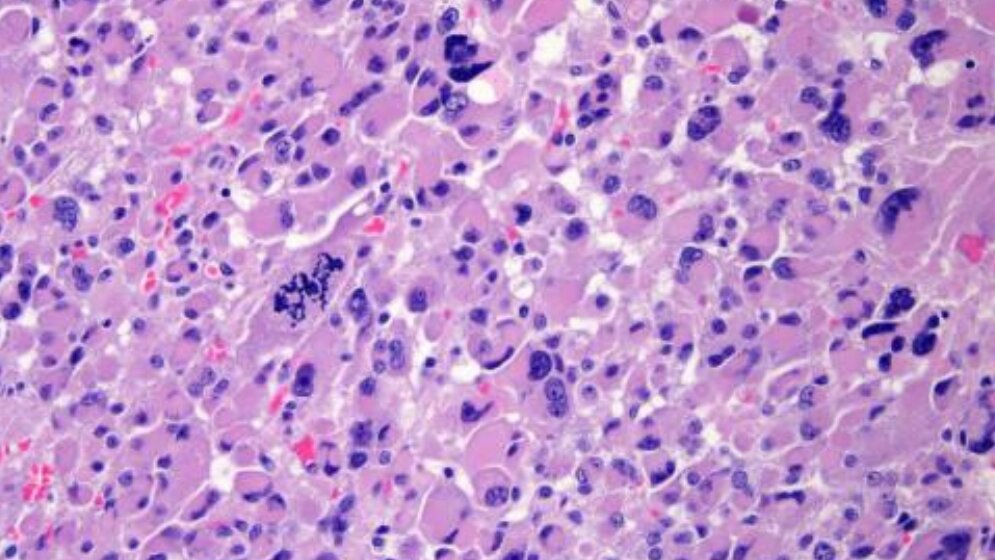

Forschergruppen aus 39 Institutionen in Europa, Nordamerika, Südamerika und Australien haben Proben von 91 Nebennierenkarzinomen gesammelt und untersucht. Sie führten eine umfassende genomische Analyse als Teil des renommierten „Cancer Genome Atlas Research Network“ durch. Ihre Ergebnisse veröffentlichten die Wissenschaftler kürzlich.

Die Studie nennt mehrere neue Gene, die zur Entstehung von Nebennierenkrebs führen. Tatsächlich konnte hier die Anzahl der bekannten genetischen Treiber durch die Studie verdoppelt werden. "Diese Daten haben Auswirkungen auf die Diagnose und die Prognose des Nebennierenrindenkarzinoms. Sie erlauben uns, tief in die Biologie der Krankheit zu blicken und zu verstehen, wie diese neuen Gen-Mutationen zu der Nebennierentumorentstehung und Progression der Erkrankung beitragen", sagt Professor Martin Fassnacht, Leiter der Endokrinologie am Universitätsklinikum Würzburg und europäischer Koordinator der Studie.

Die Studie ergab viele Erkenntnisse, sagt Dr. Silviu Sbiera, einer der beteiligten naturwissenschaftlichen Hormonforscher aus Würzburg. Eine der spannendsten Mutationen wurde im Gen „ZNRF3“ gefunden. Bis zu 20 Prozent der untersuchten Nebennierenkrebsproben weisen eine Mutation in diesem Gen auf.